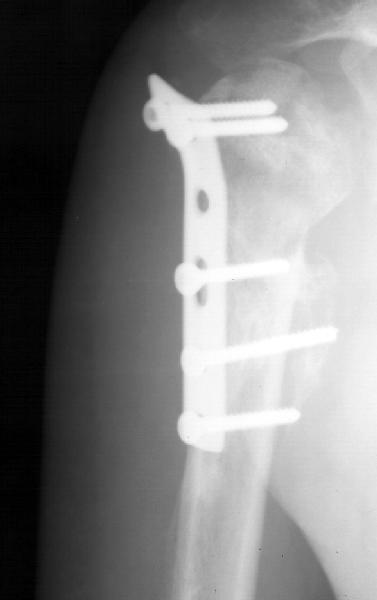

Мужчина 25 лет 16 августа 2002 г. в автоаварии получил перелом шейки плеча (снимок 1); 5 сентября в городской больнице выполнен остеосинтез пластинкой (снимок 2).К настоящему времени попал к нам на разработку ввиду выраженной контрактуры плечевого сустава. В течение последнего месяца беспокоят умеренные боли в области плечевого сустава, усиливающиеся при разработке, еще и торчит край пластинки. Нынешняя рентгенологическаякартина на снимках 3 и 4. Головка плеча уменьшается, сращение сомнительное.Кроме удаления пластинки, что еще на сегодня целесообразно сделать?Заранее спасибо.

2.Пластинка , на мой взгляд, худшее решение для перелома шейки плеча. Сама пластинка слишком груба и массивна, целая слесарня в очень чувствительной для повреждений суставе.

The current xrays indicate failure of the implant with losening. I would make sure there was no evidence of infection ( exam,ESR,CRP etc.) . I would agree with implant removal . I think this would be a suitable case for a circular ring fixator and compression, either a standard IIizarov or Taylor Spatial frame would be appropriate. I note from your previous cases that you have a high level of experience with this method.